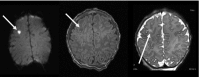

Results: Preoperative brain injury was present on HUS in 5 infants (3%) and on MRI in 44 infants (26%) (P < .001). Four of the HUS showed intraventricular hemorrhage not seen on MRI, suggesting false-positive results, and the fifth showed periventricular leukomalacia. The predominant MRI abnormality was white matter injury (n = 32). Other findings included infarct (n = 16) and hemorrhage (n = 5).

Conclusions: Preoperative brain injury on MRI was present in 26% of infants with CHD, but only 3% had any evidence of brain injury on HUS. Among positive HUS, 80% were false-positive results. Our findings suggest that routine HUS is not indicated in asymptomatic term or near-term neonates undergoing surgery for CHD, and MRI may be a preferable tool when the assessment of these infants is warranted.